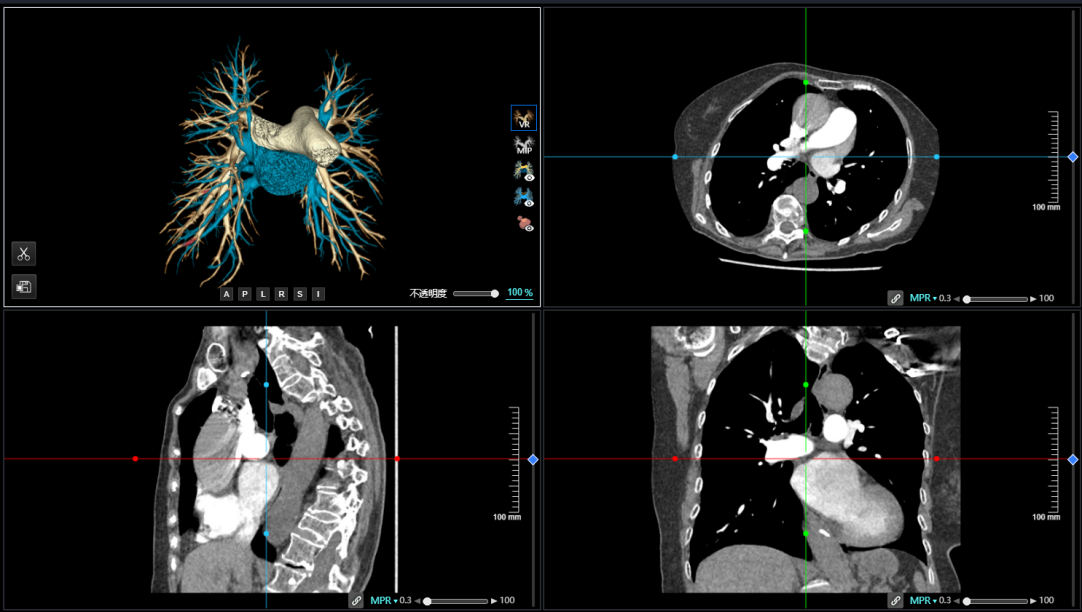

首先,该CT肺栓塞人工智能分析系统能够基于CTPA数据,快速分诊阳性肺栓塞患者,提示预警,并支持区分周围型肺栓塞和中央型肺栓塞,助力危急患者尽早进入诊疗环节。同时,支持一键智能分割、重建完整肺动脉和栓子,360°展示肺动脉走行和栓子分布位置,多种视图阅片。

同时,该CT肺栓塞人工智能分析系统也能够进行栓子高灵敏检出、解剖定位和量化分析,自动计算右心室和左心室直径比(RV/LV)和主肺动脉和升主动脉直径比(PA/Ao),以及精准计算血栓负荷分数(肺动脉栓塞指数),全面辅助诊疗,为肺栓塞的早期识别和临床风险分层提供强有力的智能工具。